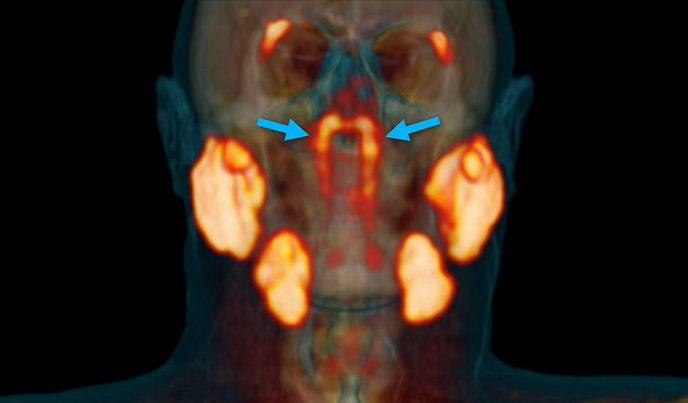

이 새로운 기관은 비인두(nasopharynx)라는 부위 뒤쪽 깊은 곳에 숨어 있었습니다.

눈에 보이지 않을 정도의 미세한 침샘이 아니라 평균 크기 3.9cm에 달하는 커다란 침샘이었죠.

과학자들은 이 침샘이 해부학적으로 접근성이 좋지 않은 두개골 아래쪽 깊숙한 곳에 위치하고 있어서 그동안 발견되지 않을 수 있었다고 설명합니다.

참고로 이 침샘은 이관융기(torus tubarius)라고 하는 연골 위쪽에 위치하고 있었기 때문에, tubarial 침샘(tubarial salivary glands)이라는 이름이 붙게 되었습니다.